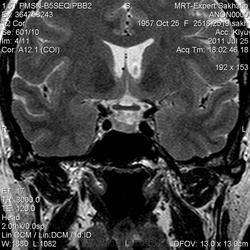

Женщина.6 лет назад выявлено образование левой доли нейрогипофиза.Пришла на контроль.

Мне самой показался случай не совсем ясным, но динамик четко показывает участок с отставанием в контрастировании, воронка смещена вправо-о чем  думать бедному начинающему специалисту?